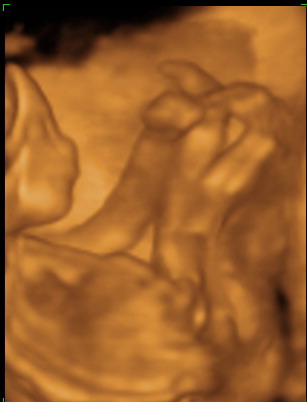

Na, visszajön a néni, UH fej fel a pocira, és mit látunk: teljesen megfordult a kis tökös! :lol:

Aztán jött az ujjszopi:

Kép .

később meg a lábfelpakolás, merthogy csak kényelmesen ám! :lol:

Szóval, produkcijjjó az volt rendesen! :lol: :lol: :lol: :lol:

Bizony az ujját szopta, tiszta nővére :) Doki bácsi szerint festett.

Nagyon édes tökitek van :) Ő is ujjszopis :wink: